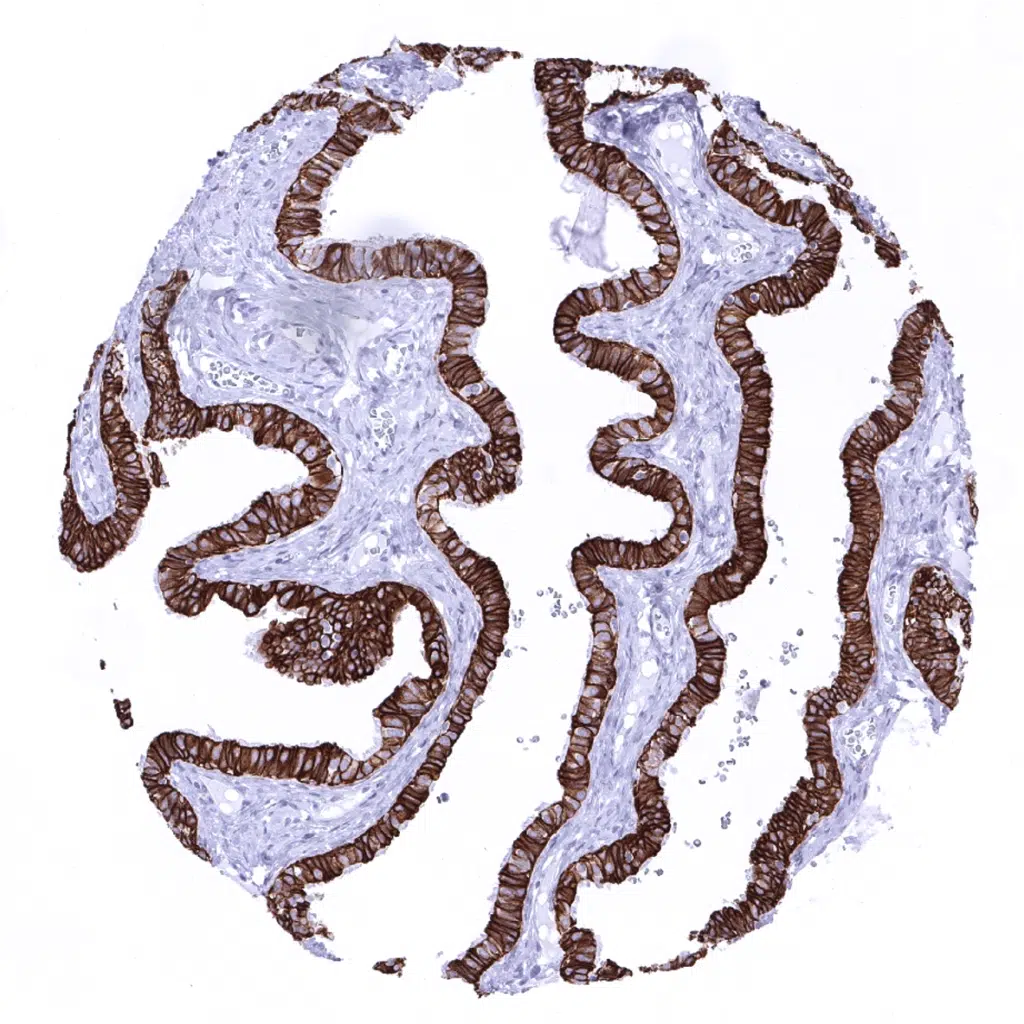

Appendix, mucosa - All epithelial cells are Cytokeratin 18 positive.